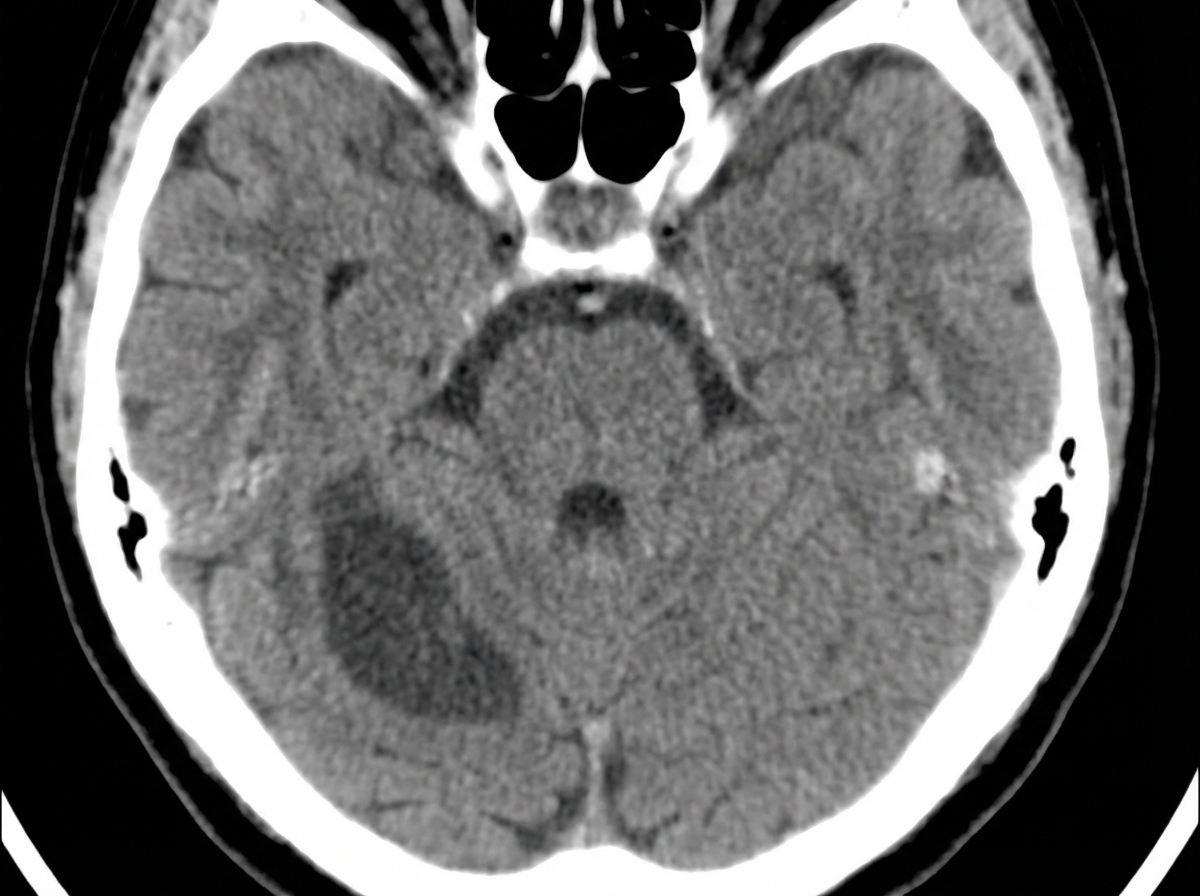

A 52-year-old man is brought to the emergency department while on vacation with a history of sudden onset vertigo and difficulty walking. He was in normal health since starting his vacation a week ago, but today he is suffering from a loss of balance, mild headache, and has had 5–6 episodes of vomiting over the last few hours. He denies fever, neck pain, head trauma, weakness, and diplopia. Past medical history is significant for hypertension and dyslipidemia. His medications include valsartan and atorvastatin, but he missed several doses since leaving for this trip. Blood pressure is 198/112 mm Hg, the heart rate is 76/min, the respiratory rate is 16/min, and the temperature is 37.0°C (98.6°F). The patient is awake and oriented to time, place, and person. Extraocular movements are within normal limits. Muscle strength is normal in all 4 extremities. An urgent head CT is ordered and shown in the picture. What additional clinical features would be expected in this patient?